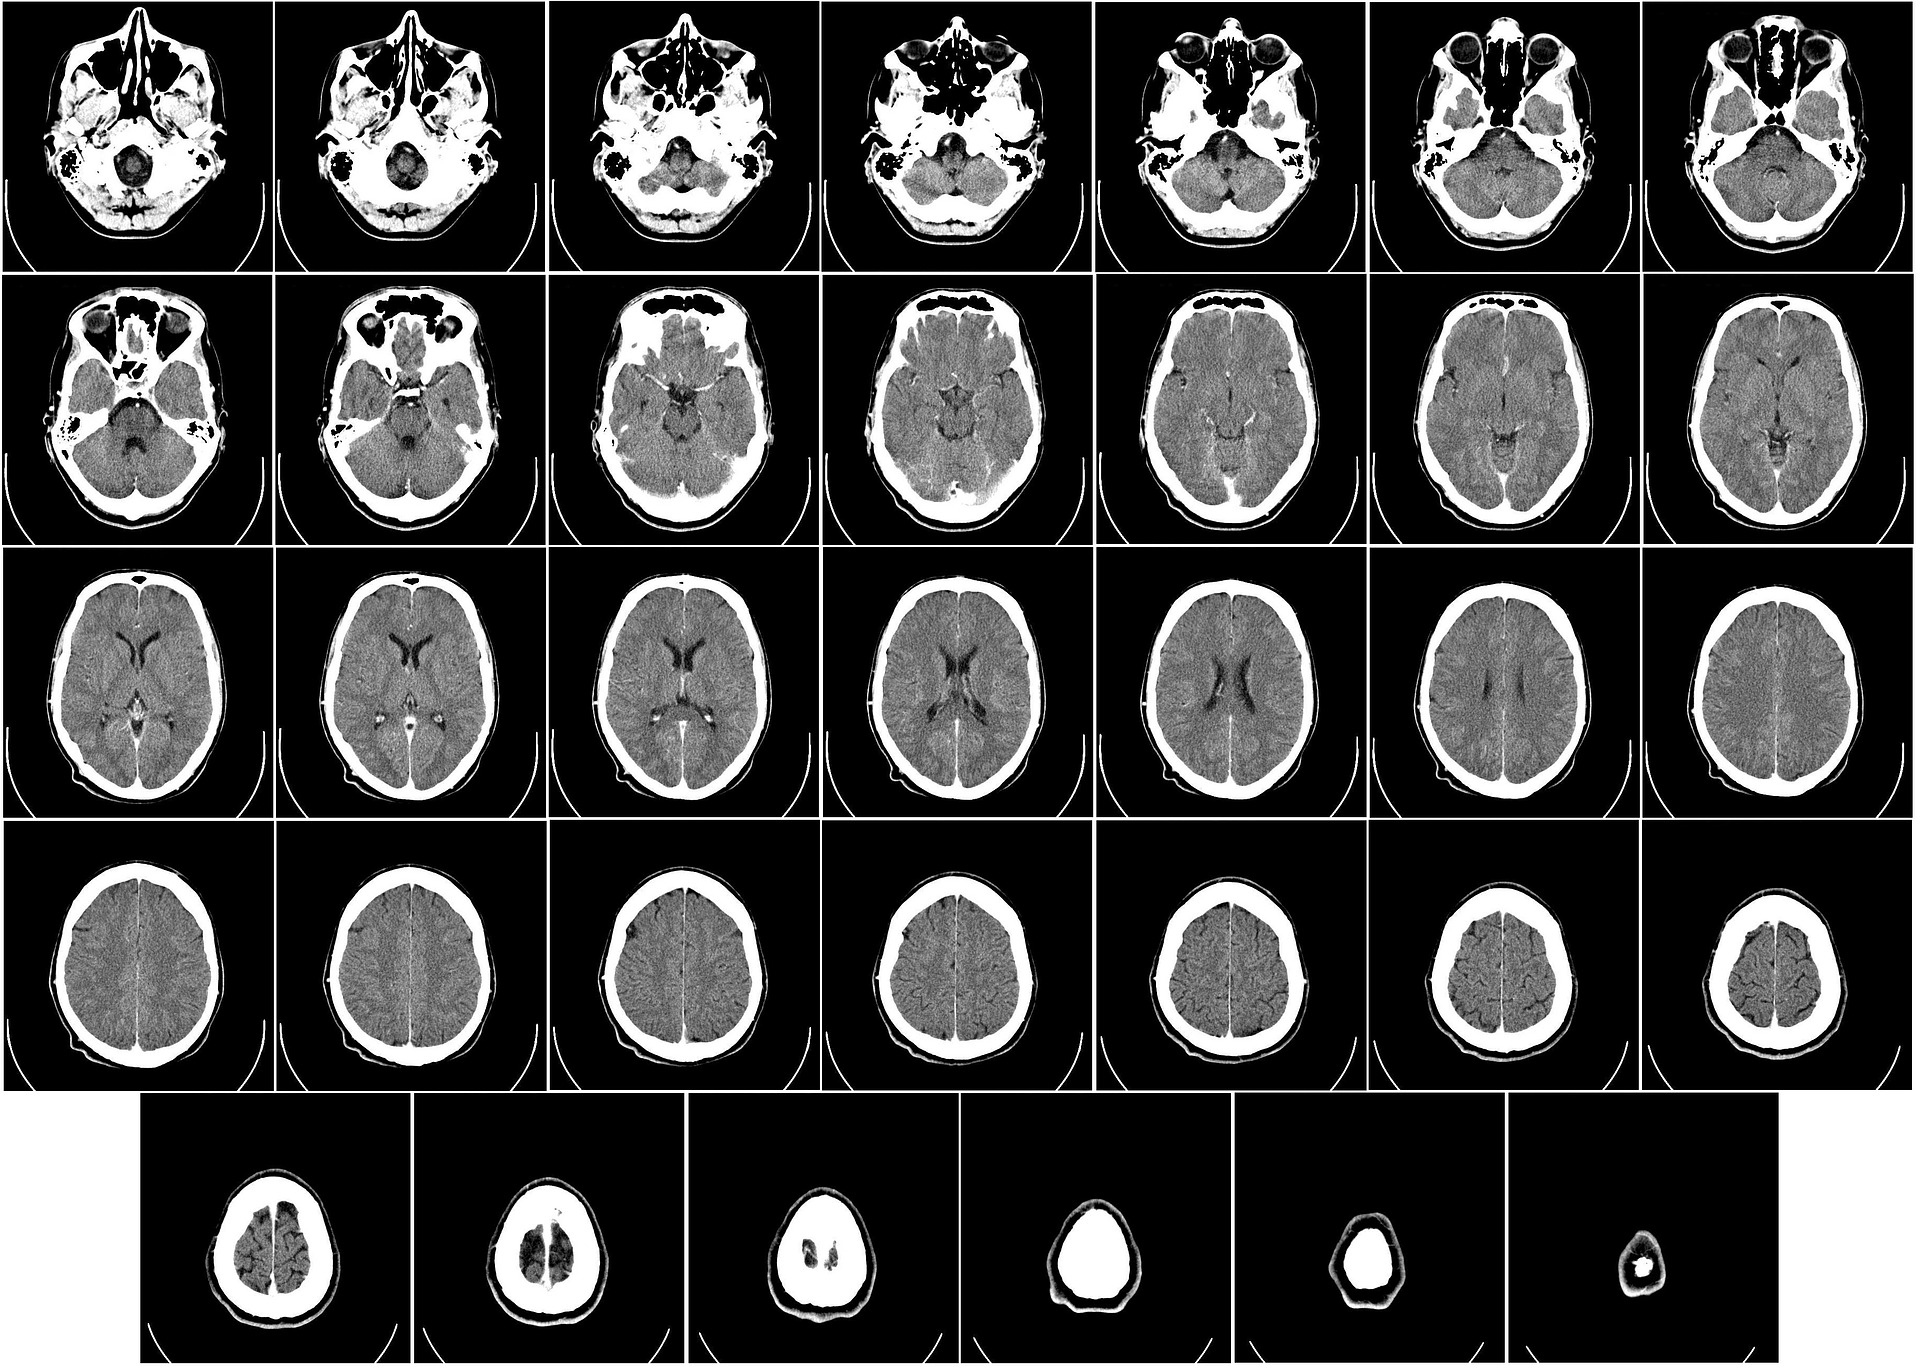

This procedure, otherwise known as thrombectomy, is carried out using a catheter inserted into the femoral artery, which is then threaded through the aorta. From there, it enters the cerebral arteries where it locates the blood clot responsible for the stroke.

A total of 48.6 percent of patients who received a thrombectomy were able to perform normal daily activities independently 90 days after the treatment. Only 13.1 percent of patients achieved a comparable level of recovery after receiving standard medical therapy. It’s important to note, however, that these findings pertain to situations where the damage is minimal.